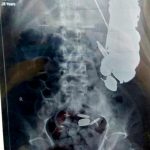

I sëmuri Maksud Khan, iu nënshtrua menjëherë operacionit në një spital në Madhya Pradesh të Indisë dhe doktorët i gjetën atij në stomak 263 monedha dhe rreth 100 gozhda dhjetëra brisqe dhe sende të tjera.

Mjekët i hoqën pacientit 7 kilogramë lëndë të huaj nga stomaku.